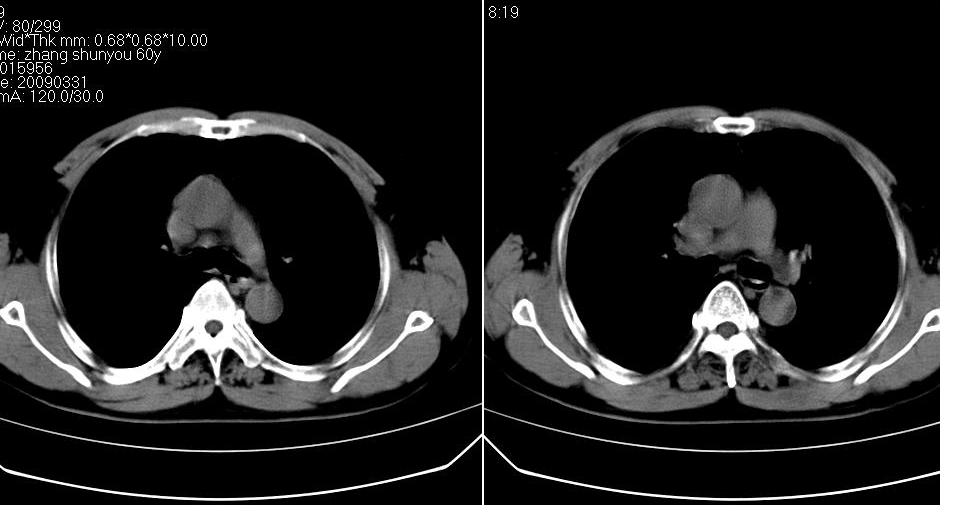

标题: CT19131:男 60岁,咳嗽,喀痰,胸闷,有吸烟史,胸部CT平扫 [打印本页]

男 60岁,咳嗽,喀痰,胸闷,有吸烟史,正常图片未上传,请谅解。

分叶状肿块,有毛刺,有晕,有粗纹理直通肺门,支持考虑周围型肺癌

首先考虑:周围型肺癌.

考虑左肺下叶周围型肺癌可能性大。